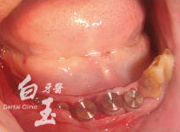

治療後